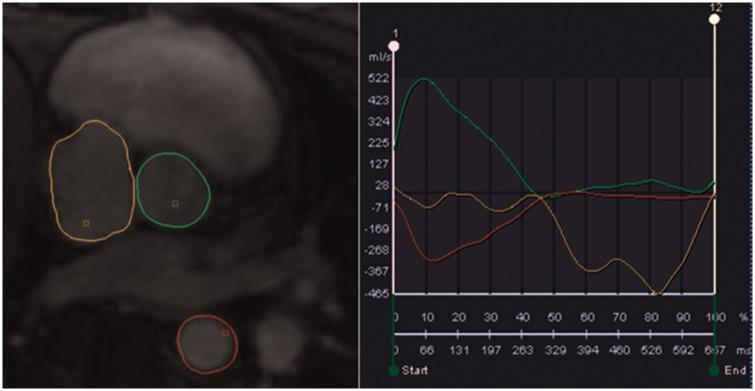

We present a case of this unusual variant of a sinus venosus defect far from the atrial roof. Haemodynamic significance of the shunt was confirmed by enlargement of right heart cavities, elevation of pulmonary artery pressure, and significant left-to-right shunting using multimodality cardiac imaging (transoesophageal echocardiography, cardiac magnetic resonance imaging, and right heart catheterization). The defect has been successfully repaired using minimally invasive axillary thoracotomy.

Partial anomalous pulmonary venous return prevalence is low and about 0.4-0.7% in autopsy series of patients with congenital heart disease. This patient's unusual variant of a sinus venosus defect with a window between a pulmonary vein and the superior vena cava far from the atrial roof shows that a sinus venosus defect is not a true atrial septum defect. Left-to-right shunting generally increases with age. Usually, surgical treatment is considered in cases of significant left-to-right shunt ( :  > 1.5-2.0) and right heart dilatation.

我们报告一例远离心房顶部的静脉窦型缺损的这种不寻常变异病例。通过多模态心脏成像(经食管超声心动图、心脏磁共振成像和右心导管检查)证实右心腔扩大、肺动脉压升高以及显著的左向右分流,从而确定了分流的血流动力学意义。该缺损已通过微创腋下开胸手术成功修复。

部分性肺静脉异位引流的患病率较低,在先天性心脏病患者尸检系列中约为0.4 - 0.7%。该患者这种不寻常的静脉窦型缺损变异,即肺静脉与远离心房顶部的上腔静脉之间存在一个窗,表明静脉窦型缺损并非真正的房间隔缺损。左向右分流通常随年龄增加。通常,在存在显著左向右分流(:> 1.5 - 2.0)和右心扩张的情况下考虑手术治疗。